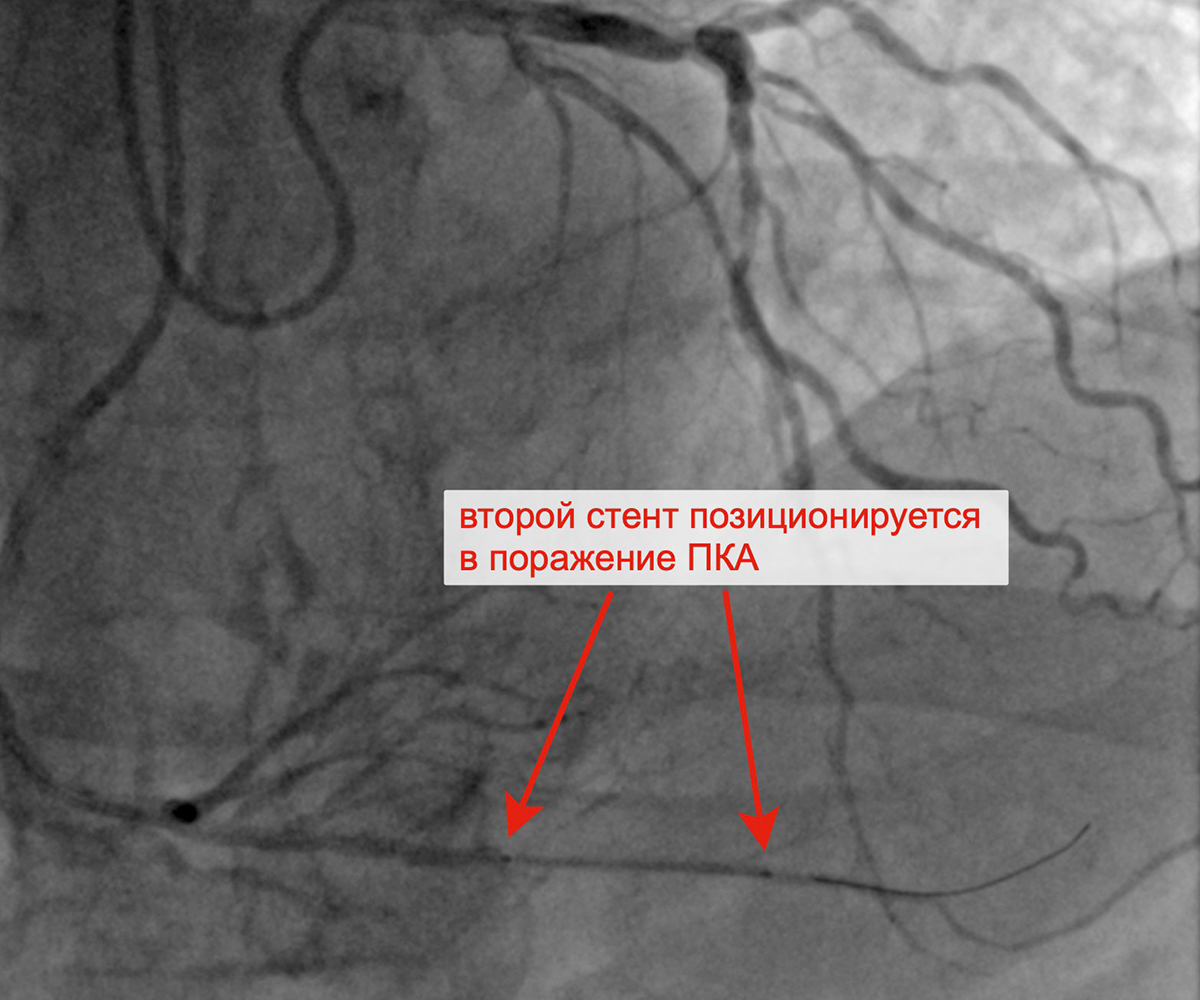

Чрескожное коронарное вмешательство (ЧКВ) на хронической окклюзии ПКА выполнялось билатеральным лучевым доступом: через левую лучевую артерию диагностическим катетером параллельно выполнялись съемки ЛКА, что позволило визуализировать через межсистемные коллатерали дистальное русло постокклюзированной ЗМЖА и контролировать процесс реканализации хронической окклюзии и проведение коронарного проводника в дистальное русло ЗМЖА. Успешно была выполнена реканализация ЗМЖА, баллонная ангиопластика и стентирование правой коронарной артерии (3 стента с лекарственным покрытием). При контрольной ангиографии: стенты и ПКА проходимы, позиционирование стентов адекватное, диссекции или остаточного стеноза в стентированных сегментах ПКА нет, кровоток TIMI 3 по ПКА и всем ветвям. Пациент был на следующий день выписан из клиники.

Позиционирование первого стента в ПКА после предилатации Позиционирование второго стента в ПКА

с билатеральным контрастированием